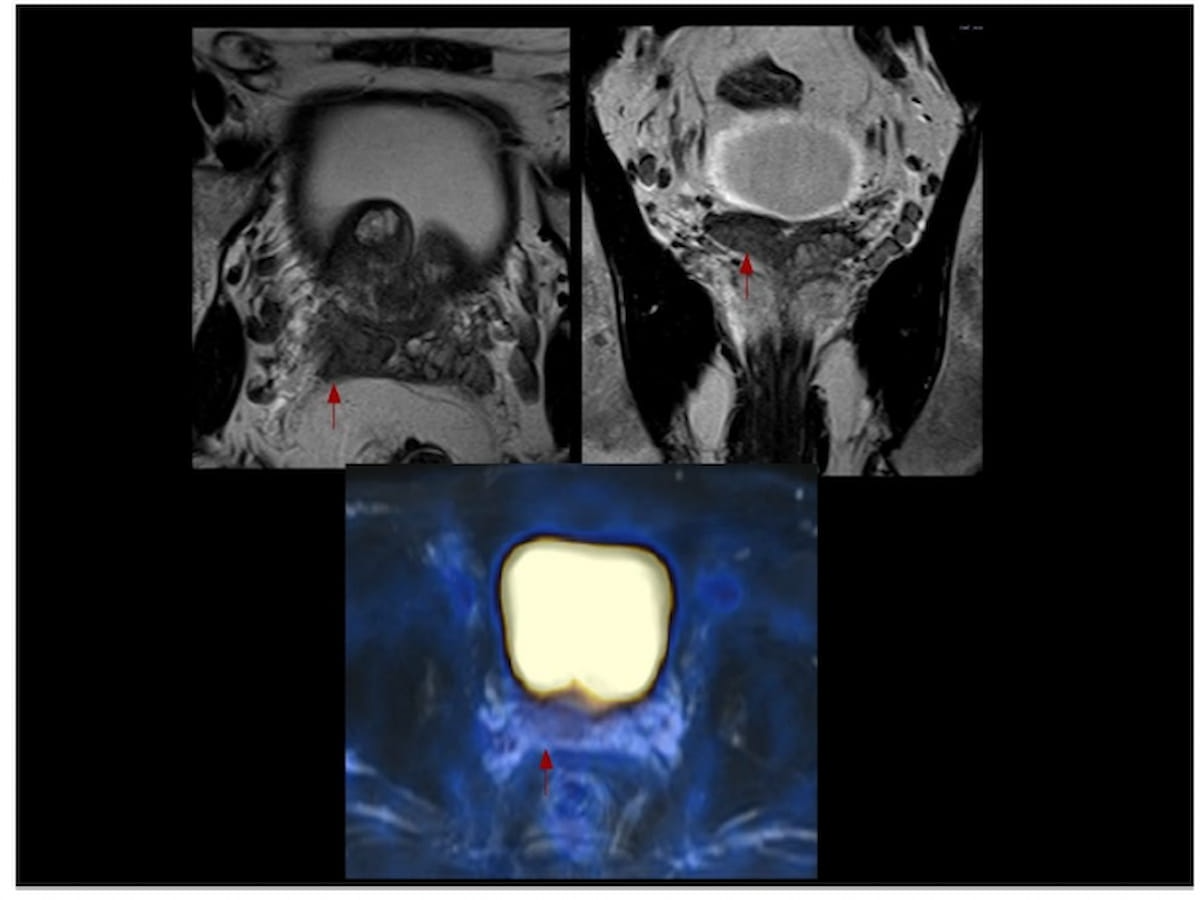

Sixty-five percent of patients with newly diagnosed high-risk prostate cancer may have extraprostatic extension on MRI, and PSMA PET/CT findings suggest those with Gleason scores of eight or higher have more than double the risk of metastasis, according to a new study presented at the European Congress of Radiology (ECR).